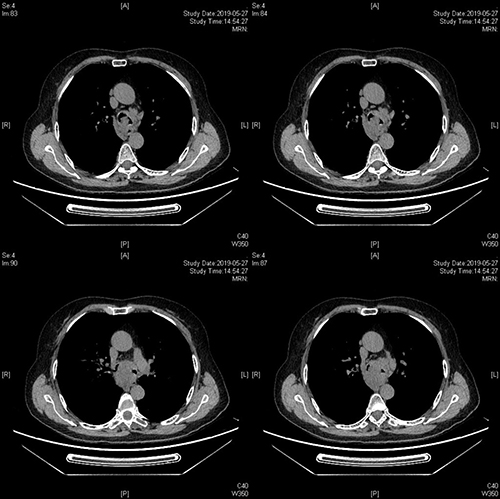

在予以隆突、左、右主支气管圈套、电切及氩气反复治疗后,病人脉氧从75%升至95%,同时病人也从半卧位状态改为平卧位。

治疗以后可见左、右主支气管远端完全通畅,肿瘤原发于隆突位置。